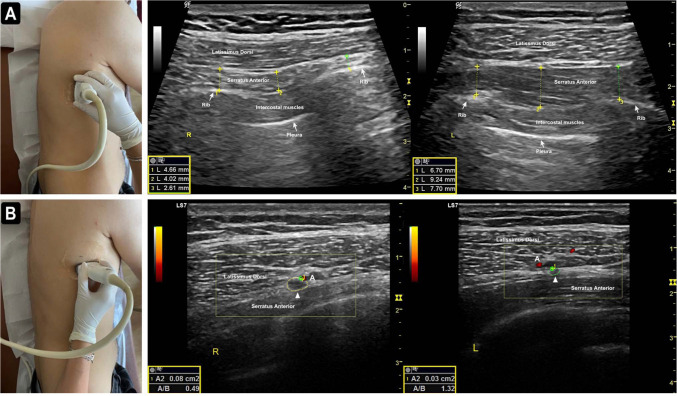

The most common etiologic cause of winged scapula (WS) is paralysis of the serratus anterior muscle (SAM), typically due to an injury of the long thoracic nerve (LTN), often associated with overhead activities, including heavy weightlifting. Herein, we reported a 30-year-old male patient with WS secondary to an LTN lesion caused by carrying weight under the armpit, rather than overhead, which differs from previous reports regarding the anatomical site and cause of the LTN lesion. The ultrasonographic technique used to evaluate distal lesions of the LTN was described in detail, with the SAM thickness significantly reduced and the cross-sectional area of the LTN increased on the symptomatic side. Electroneuromyography revealed an acute/subacute, mild partial axonal lesion of the LTN, with ultrasonographic evaluation pinpointing the exact anatomical location of the lesion. Ultrasonography should be the first imaging modality used to support electrophysiological studies and evaluate the affected nerves and muscles to reveal precise anatomical localization.